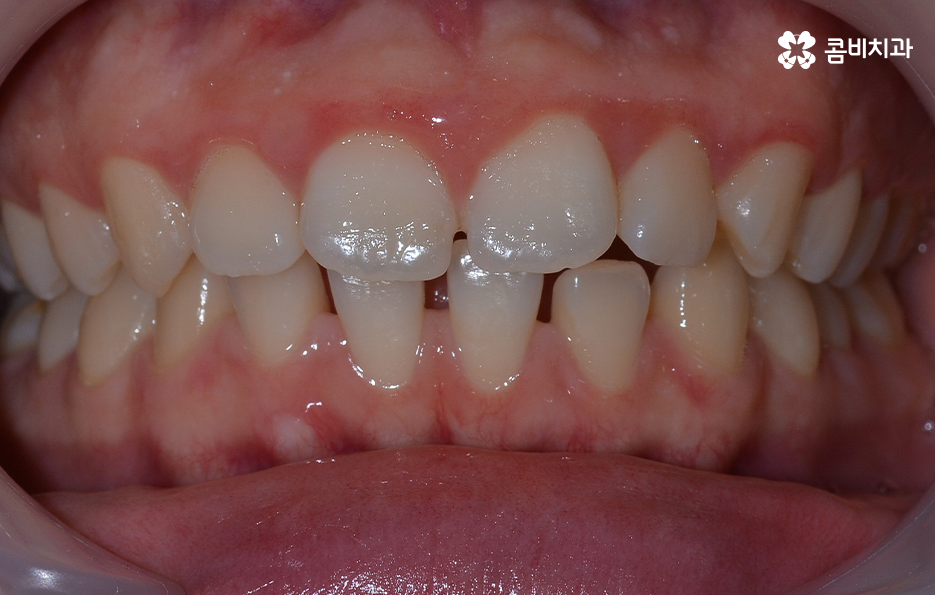

오늘 소개드릴 케이스의 경우 아랫니가 비교적 작기 때문에 교정을 통해 모아주고 윗니의 경우 측면으로 볼 때 더 잘 느껴지겠지만 다소 돌출된 상태이기 때문에 윗니는 발치를 통해 치아 이동 공간을 확보하여 돌출된 앞니를 안쪽으로 모아준 사례로 볼 수 있는데요

아랫니의 경우 치아 사이가 벌어져 있기 때문에 치아를 이동시킬 수 있는 공간이 이미 확보된 상태이고 윗니는 다소 돌출된 앞니를 안쪽으로 들어오게 하면서 심미선을 얼굴형에 조화롭게 맞출 수 있으며 그와 동시에 윗니와 아랫니의 교합도 고려한 치료 계획을 세운 것으로 간단하게 말씀드릴 수 있어요

사진으로 보더라도 아랫니 사이가 눈에 띄게 벌어져 있는 것을 확인할 수 있어요. 보통 웃을 때는 윗니 위주로 보이긴 하지만 아랫니가 이정도로 벌어져 있는 경우에는 콤플렉스로 여겨질 수 있어요